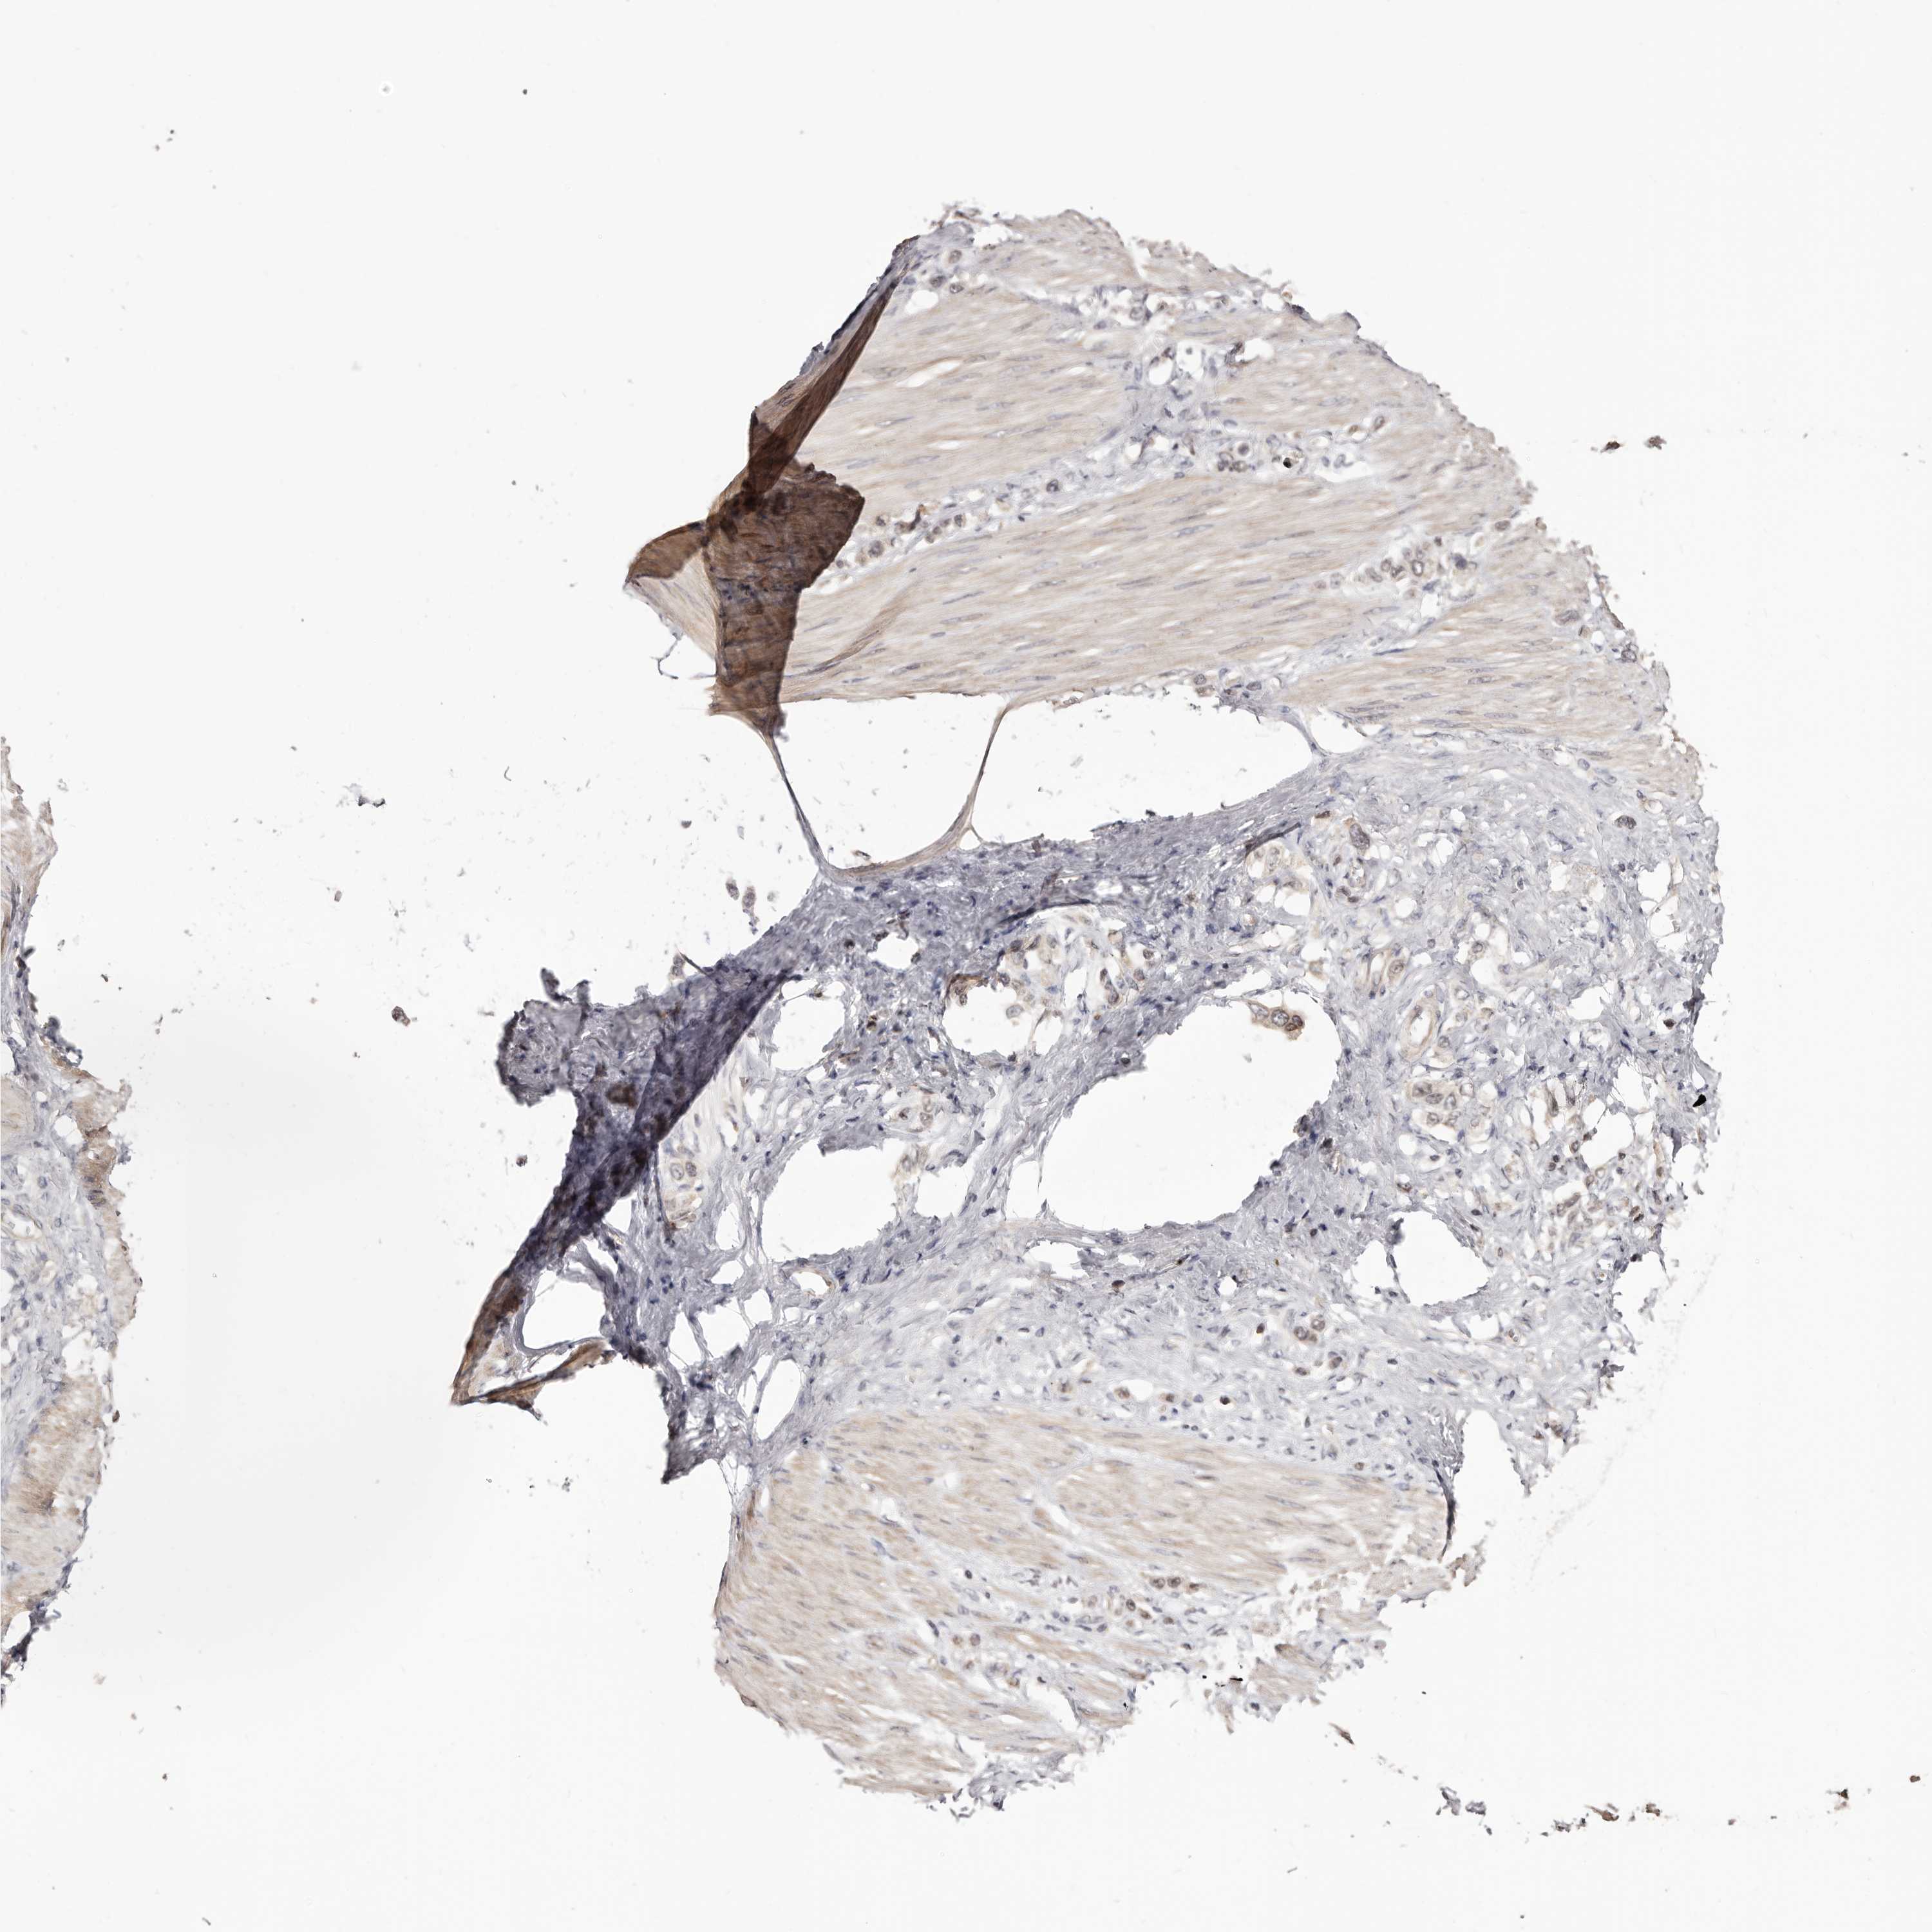

STOMACH CANCER - Protein expressioni

A mouse-over function shows sample information and annotation data. Click on an image to view it in a full screen mode. Samples can be filtered based on level of antibody staining by selecting one or several of the following categories: high, medium, low and not detected. The assay and annotation is described here.

Antibody stainingi

Antibody staining in the annotated cell types in the current human tissue is reported as not detected, low, medium, or high, based on conventional immunohistochemistry profiling in selected tissues. This score is based on the combination of the staining intensity and fraction of stained cells.

Each image is clickable and will lead to virtual microscopy that enables deeper exploration of all samples and also displays staining intensity scores, fraction scores and subcellular localization as well as patient and tissue information for each sample.

Antibody HPA003547

Staining

High

Medium

Low

Not detected

Intensity

Strong

Moderate

Weak

Negative

Quantity

>75%

75%-25%

<25%

None

Location

Nuclear

Cytoplasmic/membranous

Cytoplasmic/membranous,nuclear

Adenocarcinoma, NOS